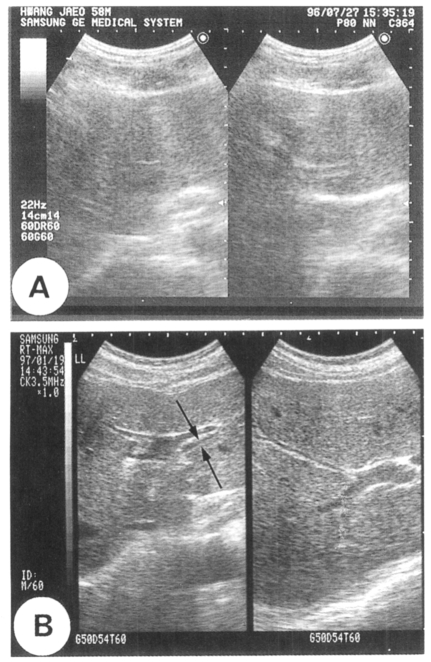

As presented in Figure 1, the sonography which showed the peripheral intrahepatic ducts was regarded as positive. On this basis, 61 (49.6%) of 123 residents, who were included more than once by both fecal examination and sonography in Koesan-gun village, were sonography-positive. Of the 123 residents, 23 were egg-positive and 100 were egg-negative. Twelve of 23 egg-positive cases (sensitivity, 52.2%) were sonography-positive and 51 of 100 egg-negative cases (specificity, 51%) were sonography-negative (Table 3).

Lim et al. (1989) recorded that the diagnosis of clonorchiasis by sonography was efficient by verifying diffuse dilatation of the intrahepatic bile ducts or thickening of the ductal wall during abdominal sonographic scanning. In the present study, sonographic diagnosis was less sensitive and also less specific than fecal examination. Its sensitivity was 52.2% and specificity was 51%.

In the endemic village in Koesan-gun, a total of 123 residents were scanned more than once, and in 61 (49.6%) the result was positive; only 12 (19.7%) of these, however, were found egg-positive and 49 (80.3%) were egg-negative. This low sensitivity and specificity of sonographic scanning may be an outcome of the light intensity of infection among the population examined; heavier infection might have resulted in higher sensitivity and specificity. Cases in which the result of sonography was false-negative might include light infection of one or two worms, and detection of these cases by any kind of method even including fecal examination is hard. In addition, most of egg positive residents who had fatty liver were found false-negative due to the increased background echogenicity from the fatty tissue.

The sonography also showed a false-positive result in 49 cases, which might have been due to visualization of the normal bile ducts, cured but scarred ducts or bile duct pathology resulting from other diseases. This high false-positive rate was partly contributed by slender residents. The sonographs of slender ones were so well visualized that the small normal intrahepatic bile ducts could be easily identified to have been regarded as false-positive. Even in the non-endemic village in Pyongchang-gun, the intrahepatic bile ducts were visualized in 31.3% of the 64 scanned residents. The present frequency of sonographic visualization of the ducts indicates that the criteria for sonographic diagnosis of clonorchiasis should be amended (Lim et al., 1989). Any sonographic feature which can specify mucosal hyperplasia would be necessary for the diagnosis.

Sonographic follow-up data of cured cases did not reveal decreased positivity after praziquantel treatment. Six to 24 months later, sonography still visualized dilated bile ducts in egg negative converters (cured cases). The sonographic positive rate was 52.2% before treatment but 64.3%, 50%, 50%, and 66.7% among cured cases 6, 12, 18, and 24 months after treatment, respectively. Total 20 of 35 cured cases (57.1%) were sonographic positive. This result demonstrates that for the differentiation of cured clonorchiasis, sonography is less useful. An animal experiment suggested the possibility of residual positive sonographic findings after treatment (Hong et al., 1994). Since abdominal sonography reflects not the worm but pathological changes in the bile duct (Lim et al., 1989) and the changes were found pathologically irreversible even after cure by praziquantel treatment (Lee et al., 1987), the sonographic differentiation has been expected hard. The present study confirmed that the sonographic finding of infected bile ducts remained for more than two years after treatment.